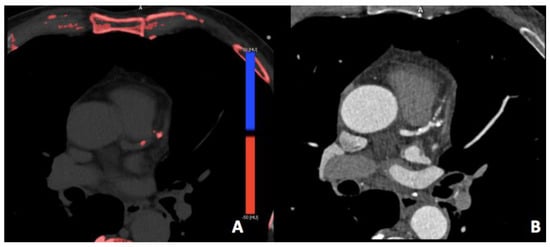

3.3. Virtual Calcium Subtraction

- Allmendinger, T.; Nowak, T.; Flohr, T.; Klotz, E.; Hagenauer, J.; Alkadhi, H.; Schmidt, B. Photon-Counting Detector CT-Based Vascular Calcium Removal Algorithm: Assessment Using a Cardiac Motion Phantom. Investig. Radiol. 2022, 57, 399–405. [Google Scholar] [CrossRef]

- Sartoretti, T.; Eberhard, M.; Nowak, T.; Gutjahr, R.; Jost, G.; Pietsch, H.; Schmidt, B.; Flohr, T.; Alkadhi, H.; Euler, A. Photon-Counting Multienergy Computed Tomography with Spectrally Optimized Contrast Media for Plaque Removal and Stenosis Assessment. Investig. Radiol. 2021, 56, 563–570. [Google Scholar]

- De Santis, D.; Jin, K.N.; Schoepf, U.J.; Grant, K.L.; De Cecco, C.N.; Nance, J.W.; Vogl, T.J.; Laghi, A.; Albrecht, M.H. Heavily Calcified Coronary Arteries. Investig. Radiol. 2018, 53, 103–109. [Google Scholar]